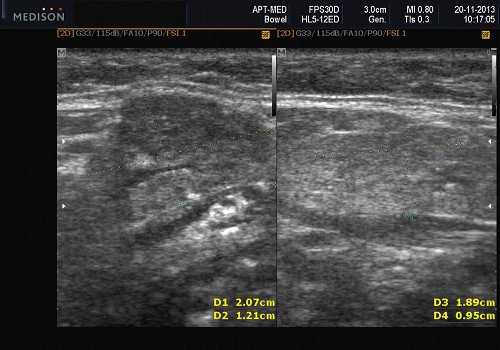

- Лучший диагностический признак на УЗИ слюнной железы - Увеличенное солидное образование околоушной или поднижнечелюстной железы

- Размер 1-5 см.

- Серошкальное УЗИ. Одиночное солидное образование в паренхиме околоушной или подчелюстной железы. Может иметь хорошо выраженные, дольчатые или плохо очерченные / инфильтративные границы. Гипоэхогенная структура по отношению к паренхиме слюнной железы. Общее улучшение ультразвукового изображения задних структур. Иногда центральный кистозный компонент представляет некроз. Могут наблюдаться связанные аномальные интрапаротидные, перипаротидные, шейные лимфатические узлы

Визуализация. Общие особенности. Само по себе ультразвуковое сканирование метастазов в околоушные лимфоузлы неспецифична. Одиночные или множественные околоушные образования. Хорошо выраженный или плохо выраженный лимфоузел (экстранодальное распространение), однородный или неоднородный с внутренним некрозом. На УЗИ с ЦДК внутриузловая васкуляризация или усиление кровотока. Патология связана с известным первичным раком, часто в прилегающей коже или региональной области головы и шеи. Околоушные и перипаротидные узлы: узловая станция 1-го порядка при плоскоклеточной карциноме кожи (ПКК) и меланоме латеральной части волосистой части головы, ушной раковины / наружного слухового прохода и передней части лица

Размер. Обычно 1-3 см

Серошкальное УЗИ. Одиночные или множественные гипоэхогенные образования в известном распределении внутрипаротидных лимфоузлов. Хорошо выраженный или слабо окаймленный (экстранодальное распространение). Экстранодальное распространение. Обратите внимание на местную инвазию интрапаротидной наружной сонной артерии (ВСА), ретромандибулярной вены или экстрапаротидных мягких тканей. Аномальная внутренняя архитектура ± эхогенные ворота. Однородный или неоднородный вид с внутренними кистозными участками в некротических узлах ± метастазы в шейные лимфатические узлы